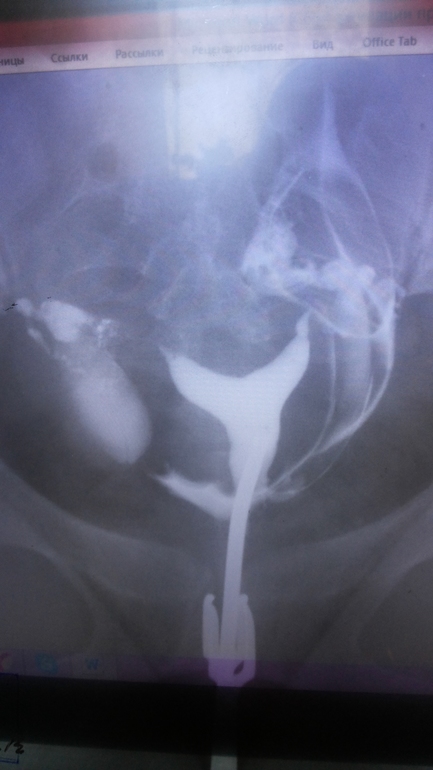

слева не оч...((а так...сказать что все запущено - нельзя.только по снимку ведь нельзя делать окончательные выводы.[removed](function () {

вот мой снимок 4 года назад делала примерно! что-то не грузится

Это снимок проходимости труб, мне такой делали. Мне кажется матку раствор заполнил, а труб не видно. Если быраствор заполнил трубы они бы тоже белого цвета были как и матка, но может на фото не видно,т.к. они тоненькие

правой трубы не видно видно как она увеличенна ....а левая действительно тоненькая но ее видно просто она витая и припаялась к матке (так мне врач объяснял , который делал), но жидкость то вышла вся в полость и снимок один делали...сестра гинеколог(не знаток в ГСГ)говорит что если жидкость вышла в полость значит все хорошо и еще одна врачица так же говорит....